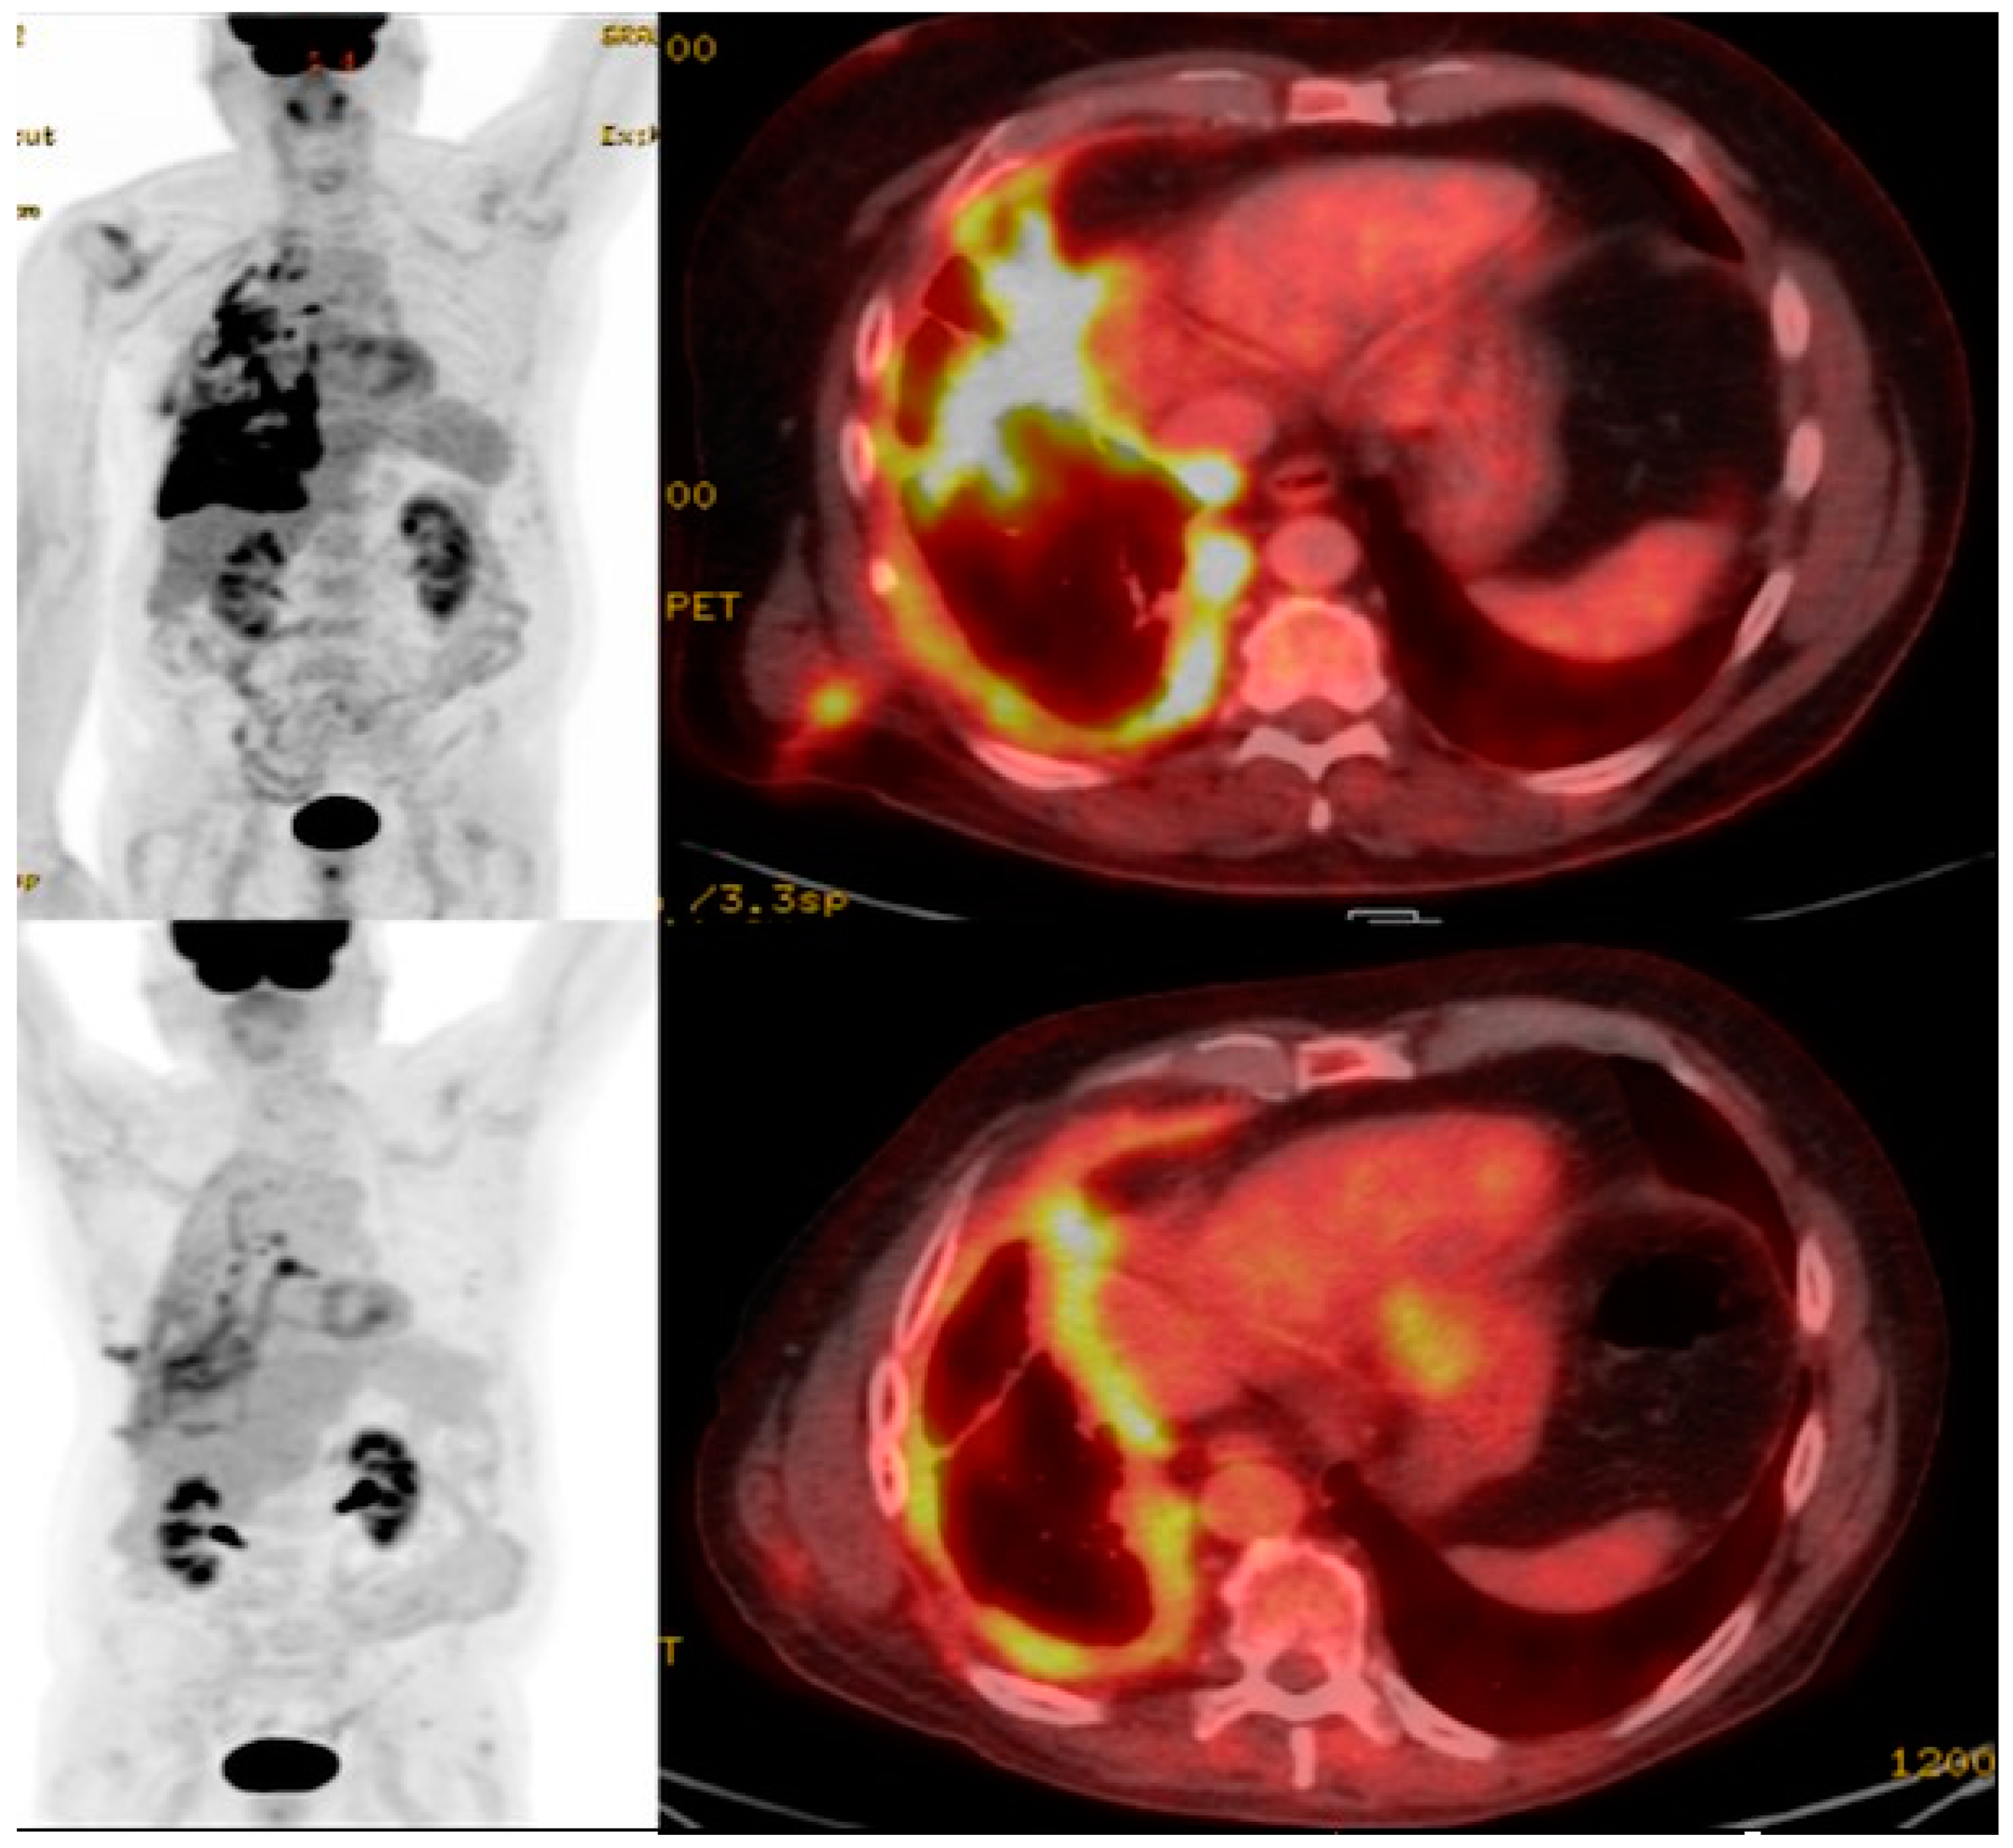

11. Imaging CAR T Cell Action

- Emami-Shahri, N.; Foster, J.; Kashani, R.; Gazinska, P.; Cook, C.; Sosabowski, J.; Maher, J.; Papa, S. Clinically compliant spatial and temporal imaging of chimeric antigen receptor T-cells. Nat. Commun. 2018, 9, 1081. [Google Scholar] [CrossRef]

- Volpe, A.; Lang, C.; Lim, L.; Man, F.; Kurtys, E.; Ashmore-Harris, C.; Johnson, P.; Skourti, E.; de Rosales, R.T.M.; Fruhwirth, G.O. Spatiotemporal PET Imaging Reveals Differences in CAR-T Tumor Retention in Triple-Negative Breast Cancer Models. Mol. Ther. 2020, 28, 2271–2285. [Google Scholar] [CrossRef] [PubMed]